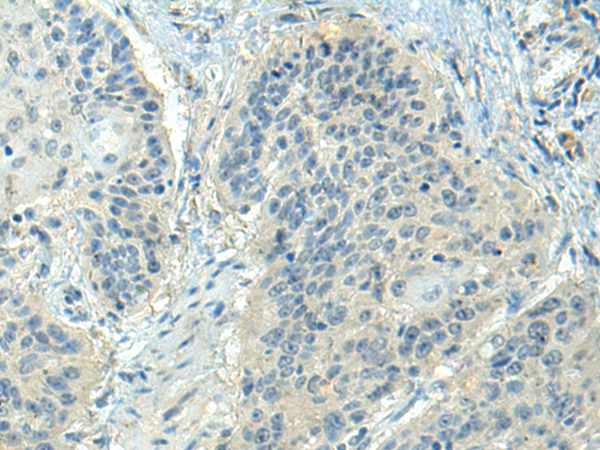

分类: 科研抗体货号: P10832别名: ALK-SMase应用: IHC反应种属: Human, Rat